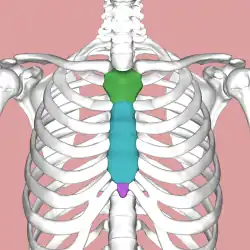

Parts of the sternum: manubrium (green), body (blue), xiphoid process (purple) | |

The sternum (pl.: sternums or sterna) or breastbone is a long flat bone located in the central part of the chest. It connects to the ribs via cartilage and forms the front of the rib cage, thus helping to protect the heart, lungs, and major blood vessels from injury. Shaped roughly like a necktie, it is one of the largest and longest flat bones of the body. Its three regions are the manubrium, the body, and the xiphoid process.[1] The word sternum originates from Ancient Greek στέρνον (stérnon) 'chest'.

The sternum is a narrow, flat bone, forming the middle portion of the front of the chest. The top of the sternum supports the clavicles (collarbones) and its edges join with the costal cartilages of the first two pairs of ribs. The inner surface of the sternum is also the attachment of the sternopericardial ligaments.[2] Its top is also connected to the sternocleidomastoid muscle. The sternum consists of three main parts, listed from the top:

- Manubrium

- Body (gladiolus)

- Xiphoid process

Manubrium

Body

Xiphoid process